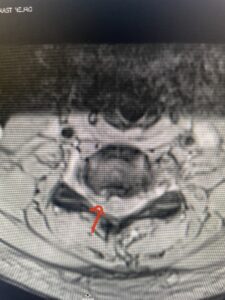

This 47-year-old male who four months prior was lifting weights developed sharp pain in his neck. After that he developed progressive numbness in his arms, neck pain and headache. He said that the right arm was worse than the left. On examination the patient had long tract weakness on the right side which included his triceps, finger extensors, hip flexors, and dorsiflexors. The patient did not have hyperreflexia. MRI (Fig. 2) demonstrated a massive, extruded disc herniation with severe cord compression. The patient because of progressive myelopathy and spinal cord compression was indicated for anterior cervical discectomy and fusion at C4-5 (Fig. 3). Patient had significant improvement of weakness and numbness post operatively.

Fig: 2b Axial T2-weighted cervical MRI demonstrating spinal cord compression from C4-5 herniated disc (red arrow)